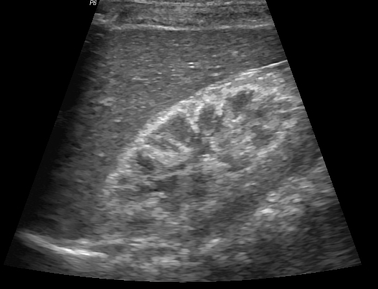

Néphrocalcinose médullaire

- Accentuation de la différenciation cortico-médullaire avec hyperéchogénicité médullaire